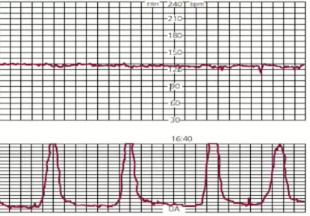

Q

Resultado dessa CTG?

A

Normal

Variabilidade dessa CTG?

Ausente/reduzida